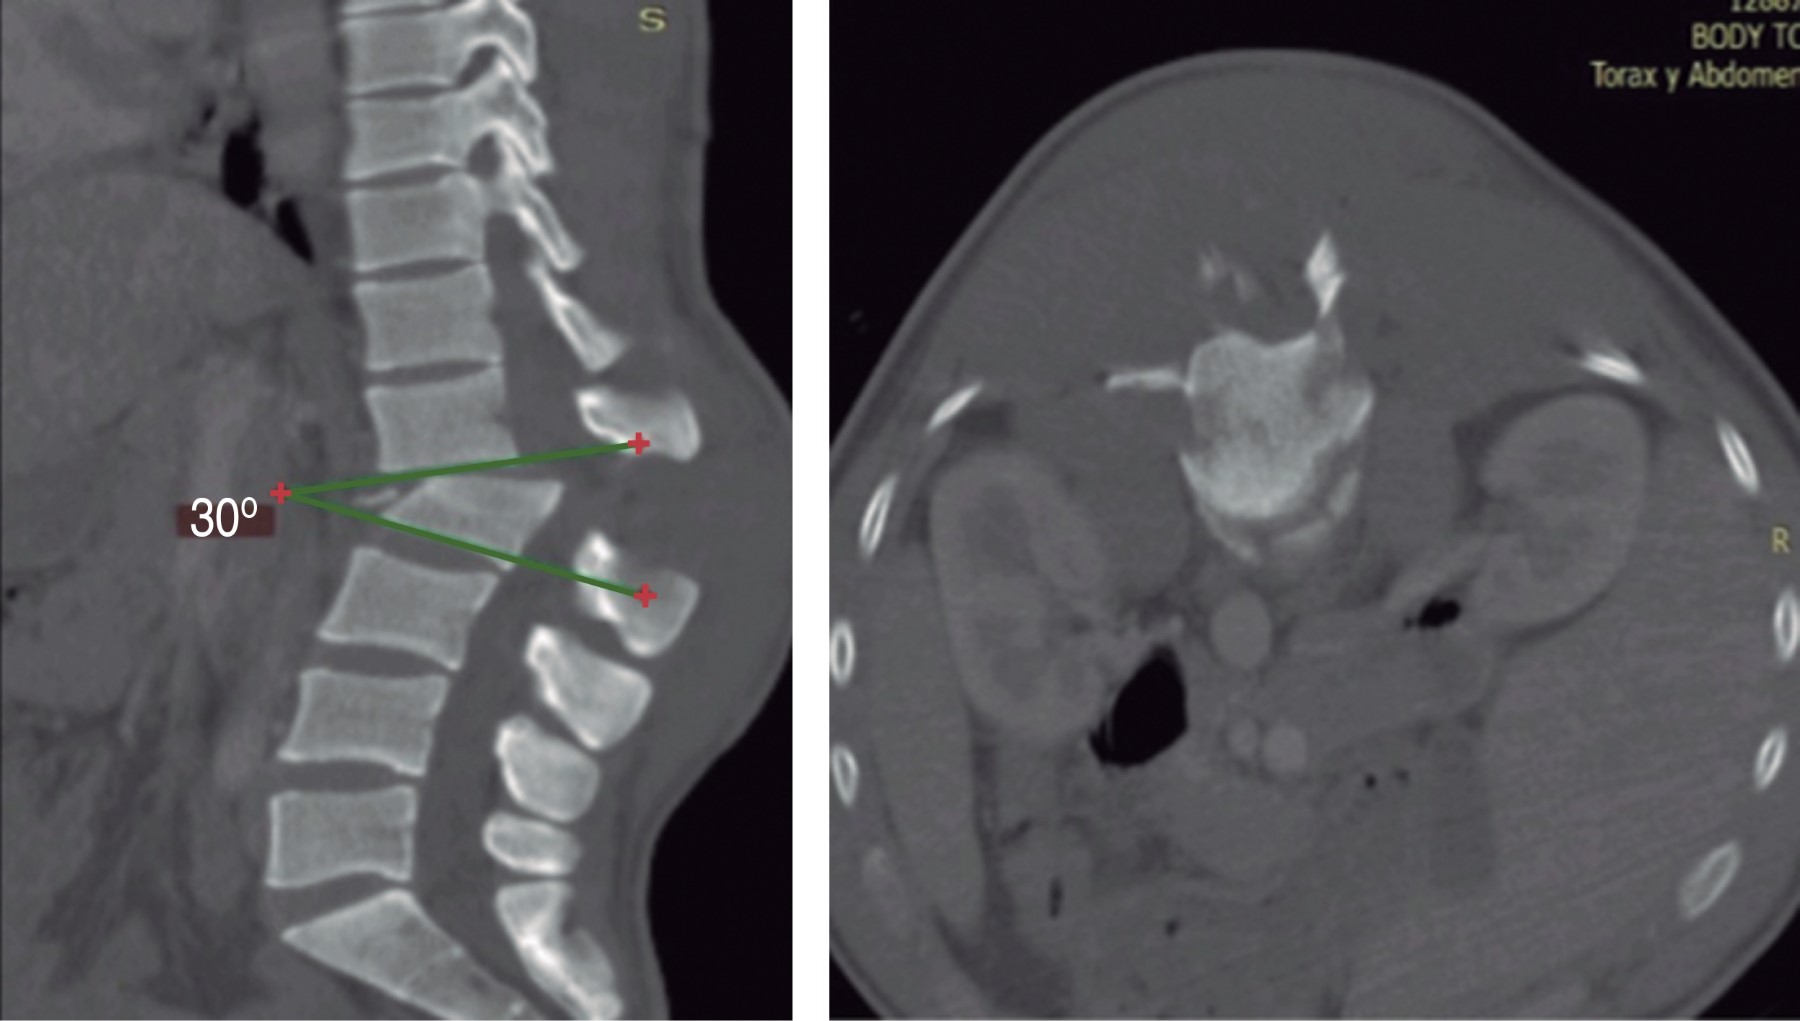

Figure 1